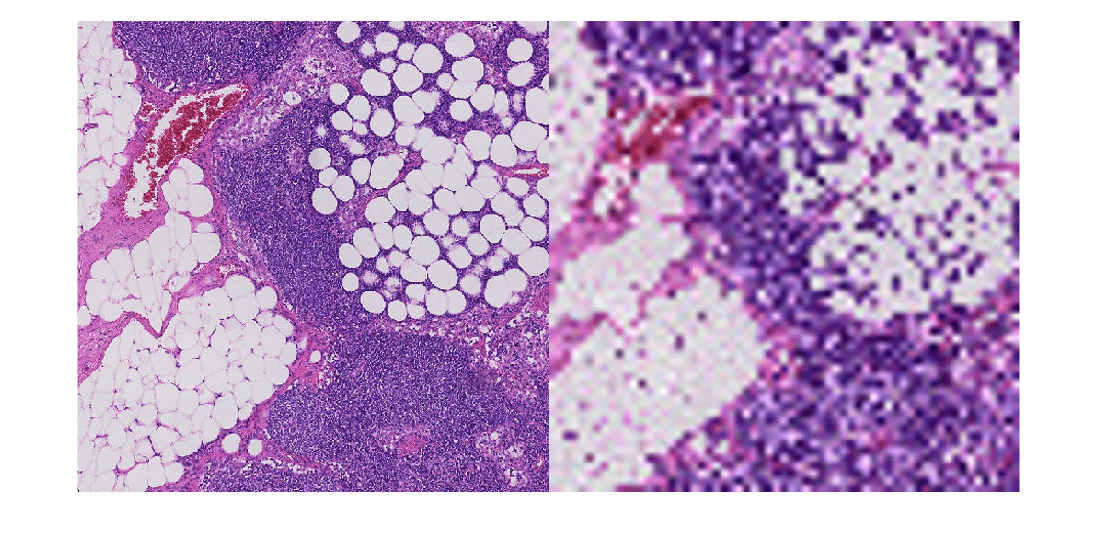

pixels = getRegion(bim,pixelStart,pixelEnd)bim, in the region

specified by pixelStart and pixelEnd.

pixels = getRegion(bim,pixelStart,pixelEnd,Level=L)L'th resolution level of the

multiresolution blockedImage object, bim.

pixelStart and pixelEnd are pixel subscripts at

the L'th resolution level.